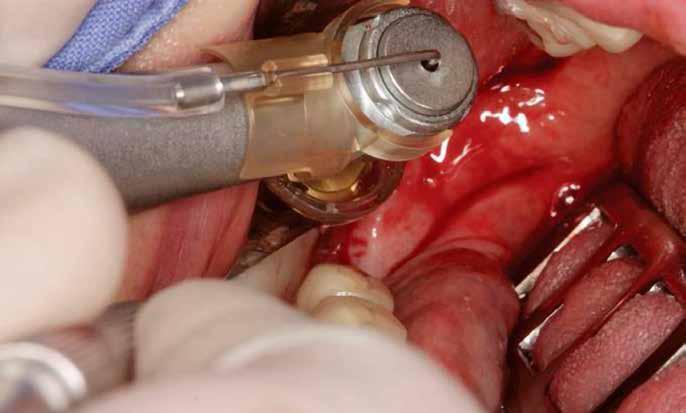

A fogak eltávolítása minimálinvazív módon történt, amelynek során a parodontális rostokat egy periotom segítségével átvágtuk, így lebenyes feltárásra nem volt szükség (3. a–b ábrák) . Az implantátumokat a frissen eltávolított fogak alveolusaiba ültettük be. A foghúzást követően minden alveolust alaposan ellenőriztünk az endodontiai, vagy parodontális eredetű gyulladásos szövetmaradványok eltávolítása érdekében, majd fiziológiás sóoldattal bőségesen átöblítettük. Megfelelő előfúrást követően a kerámiaimplantátumokat 30 fordulat/perc sebességgel és 35 Ncm behajtási nyomatékkal helyeztük be (4. a–b ábrák) . A réseket csontpótlóval töltöttük ki (Maxresorb ® 0,5–1,0 mm szemcseméret, 0,5 cm 3 térfogat, Straumann ®; 6. ábra ).

3. ábra: Intraorális kiindulási állapot. – 4. ábra: A terület intraorális nézetből. 5. ábra: A lebenyes feltárást követően laterális és vertikális csonthiány látszik a 1.4 területén. – 6. ábra: Az Easy Bone Collector egy egyedi műszer, amely trepánfúrót, belső hűtést, kerámia csapágyakat és integrált lágyrészvédelmet tartalmaz. Mindez megkönnyíti a csontlemezek eltávolítását. – 7. ábra: A semilunaris technika és az Easy Bone Collector együttes alkalmazása több kortikális csontlemez kinyerését teszi lehetővé a retromoláris régióból.